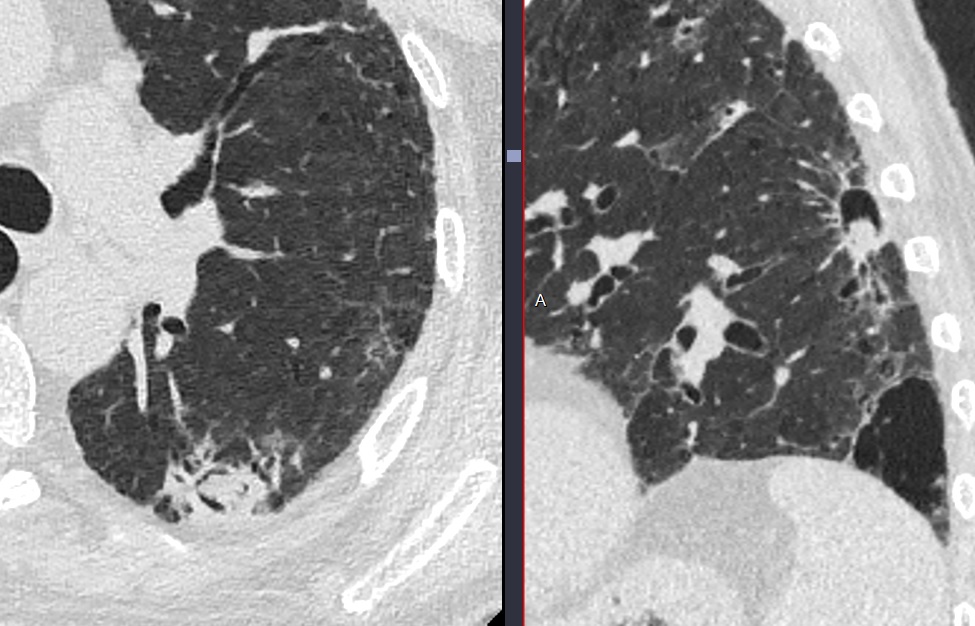

- Masse dans une cavité (signe du croissant aérique / signe de Monod)

- Peut être mobile au changement de position

- DD Cancer. Pas facile de les distinguer. Une prise de contraste >10HU de la boule favorise le cancer. L’aspergillome est declive en procubitus il va tomber

Cas

Confirmé chirurgie